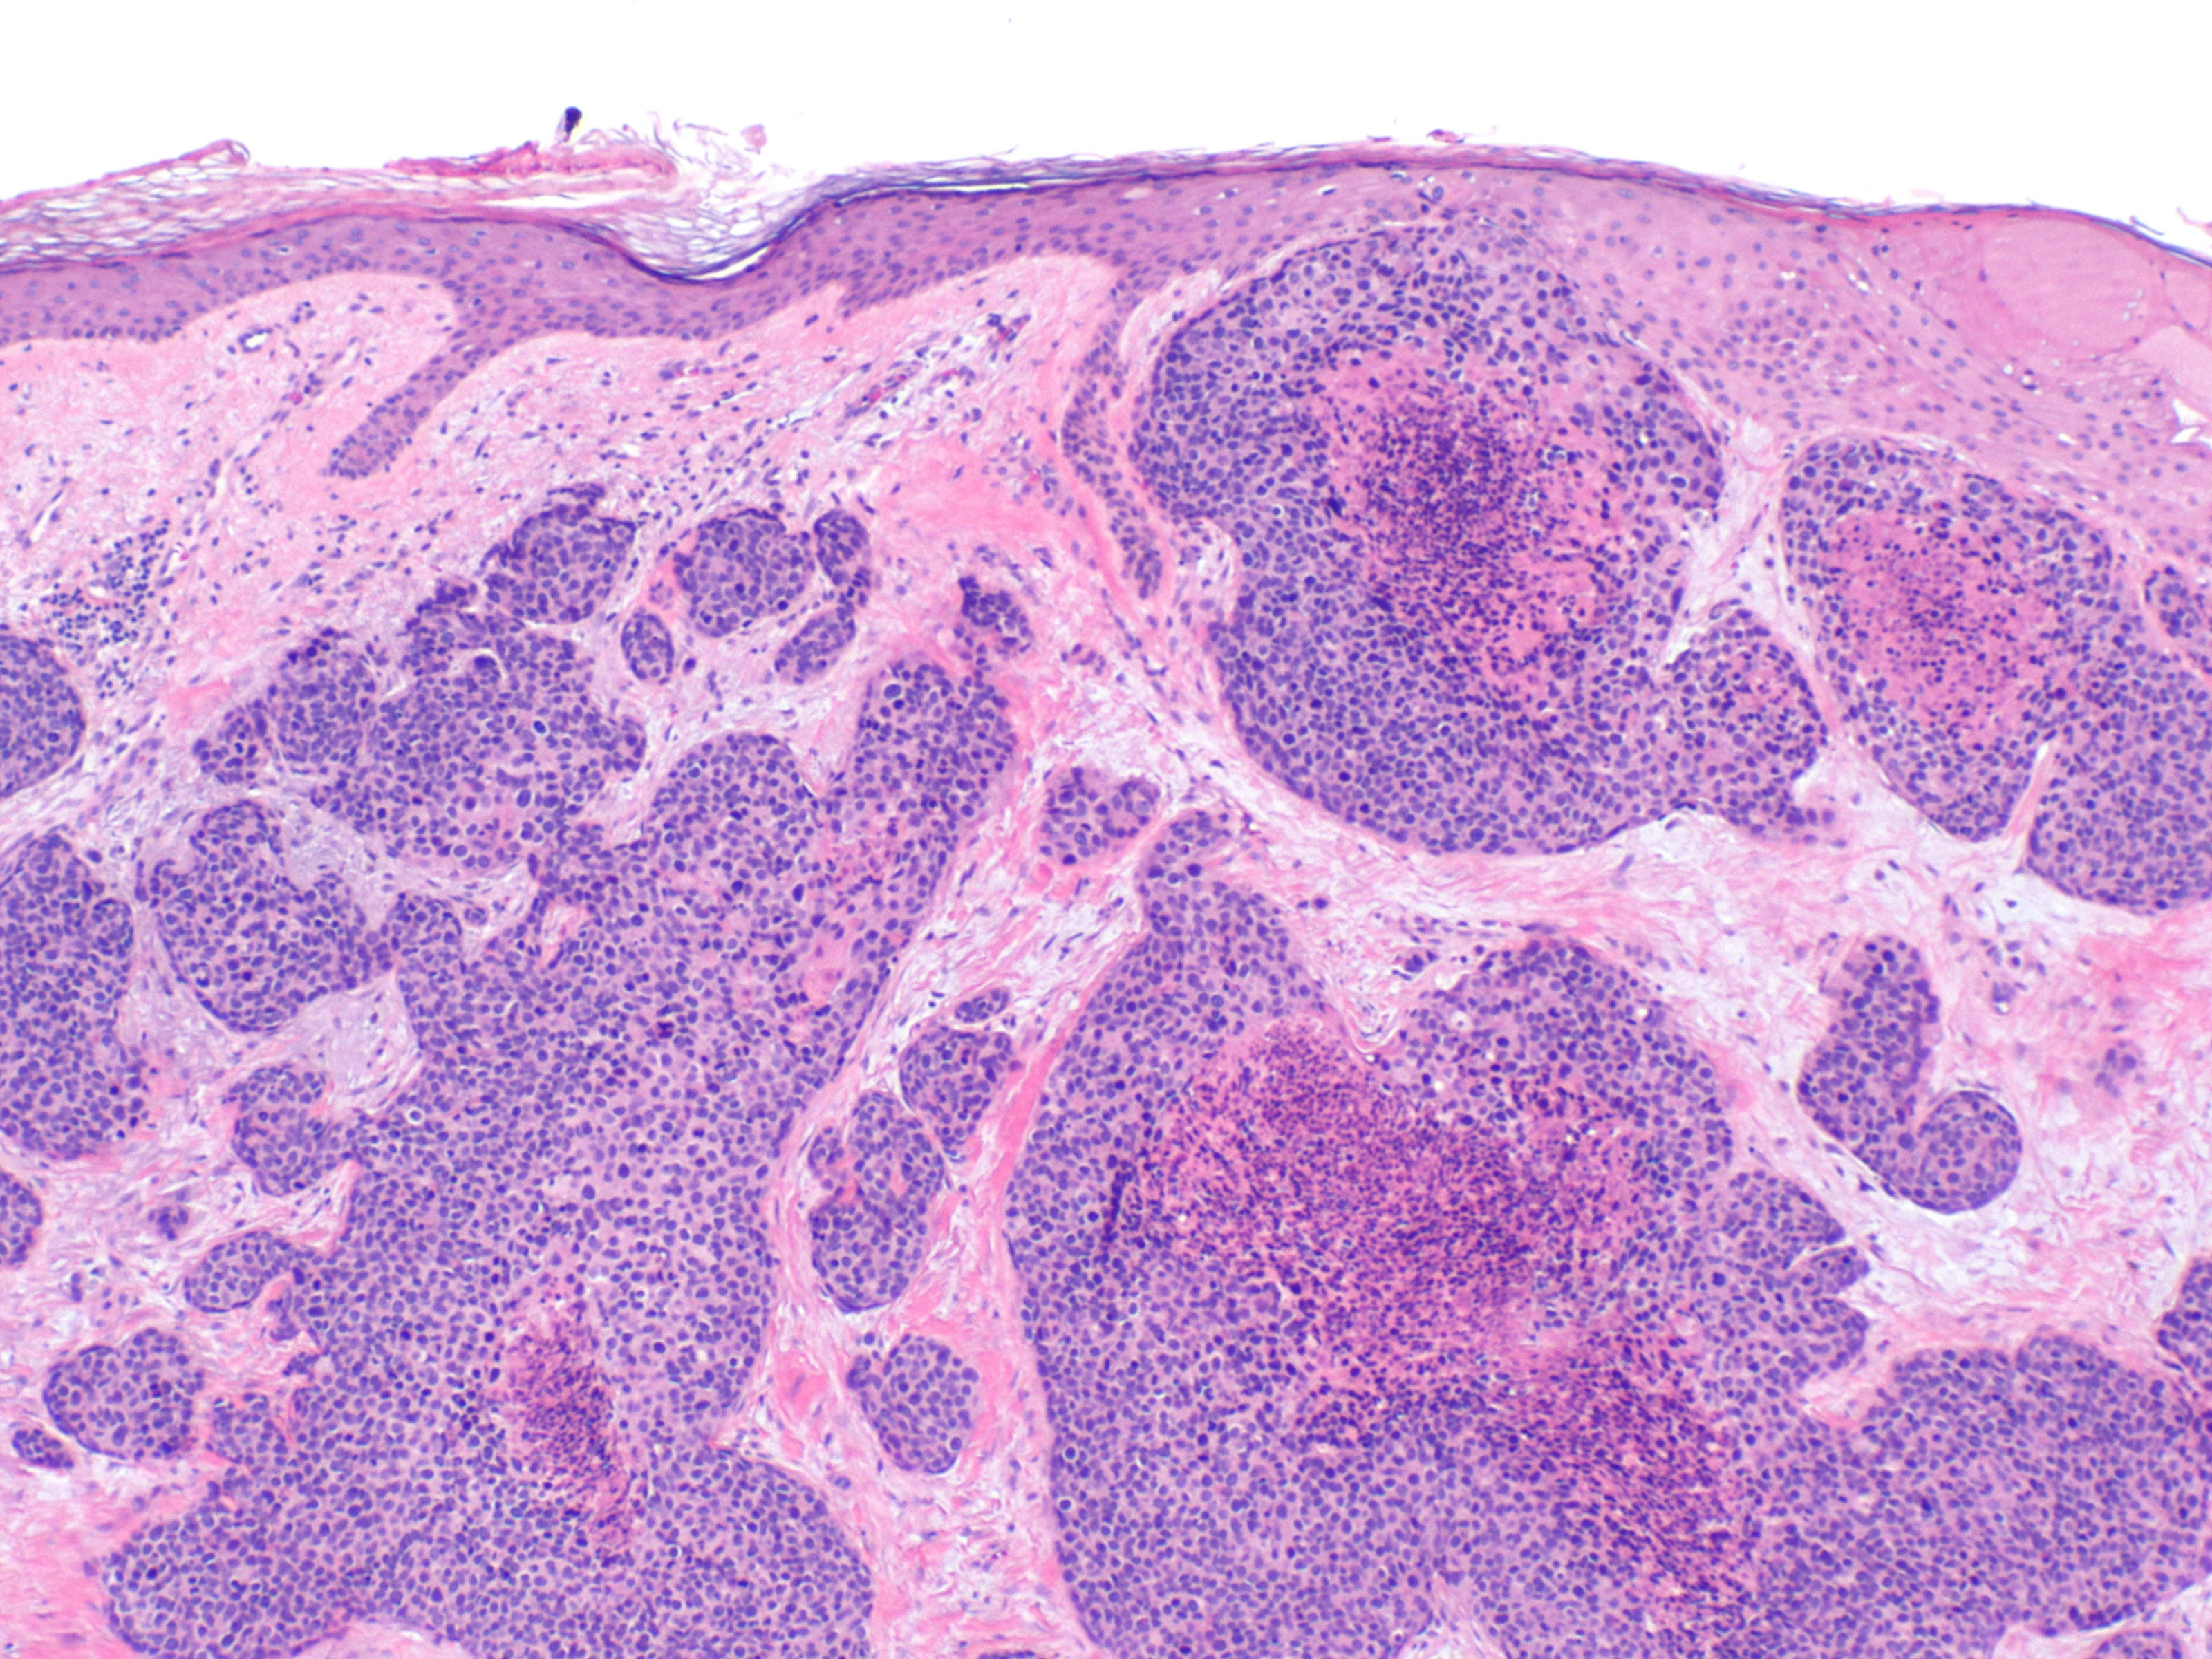

PA:

Multipele velden van basaloïde polygonale tumorcellen cellen met plaatselijk

ductale differentiatie, buis structuren met cuboïd epitheel. Uitgesproken cytologische

atypie, mitosefiguren. Soms ook squameuze differentiatie en dyskeratotische

cellen. Immunohistochemie: de ductale structuren kleuren aan met CEA (carcinoembryonic

antigen) en EMA (epithelial membrane antigen). De tumoren zijn meestal positief

voor CD117 (KIT), cytokeratin 19, c-KIT, en BerEP4. De prognose is slecht als

er invasie is van lymfbanen en vaten, meer dan 14 mitoses per high-power veld

en bij een tumordiepte > 7 mm.

| histologie

porocarcinoom |

histologie

PA-foto's: Michael Bonert (Nephron) - Wikimedia - Creative Commons License

3.0).